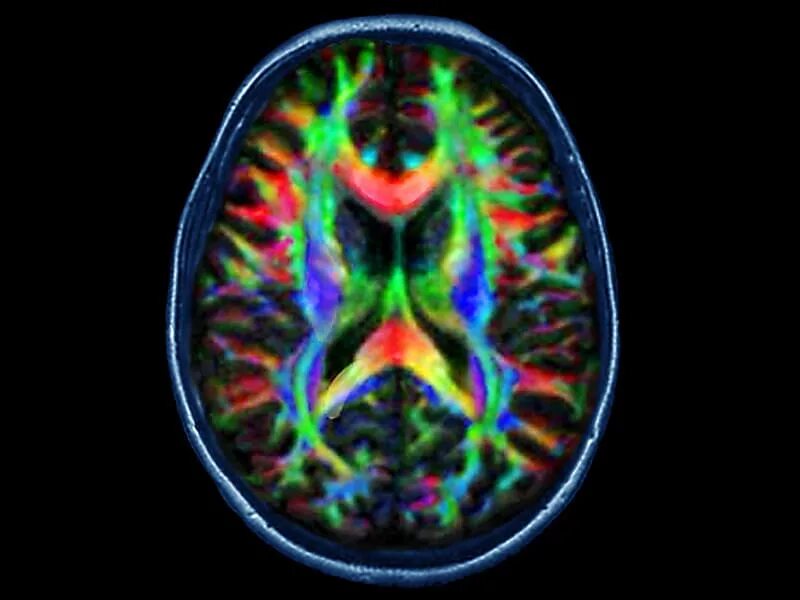

Diffusion tensor